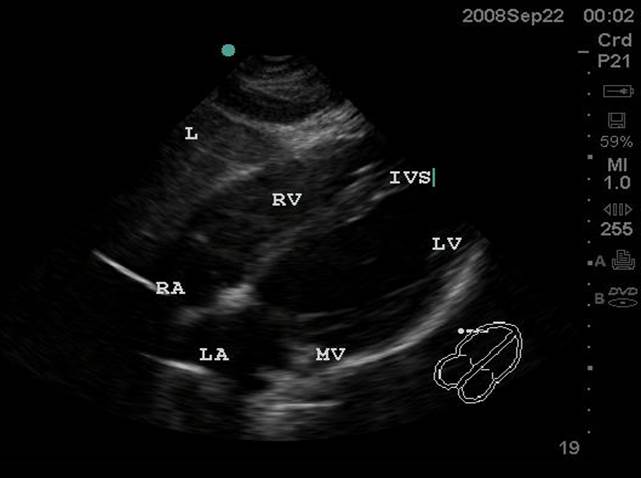

- Subxiphoid or Subcostal View: The liver is used as an acoustic window and is seen at the left of the screen and near field. The right ventricle being the most anterior is adjacent to the liver. The apex will be to the right of the screen. By fanning inferiorly, the inferior vena cava (IVC) is seen in short axis. Often the hepatic veins can be seen in the liver draining into the IVC.

- Figure 1. Subxiphoid View. RA = Right atrium. RV = Right ventricle. IVS = interventricular septum. LV = left ventricle. MV = Mitral valve. LA = left atrium. L = Liver